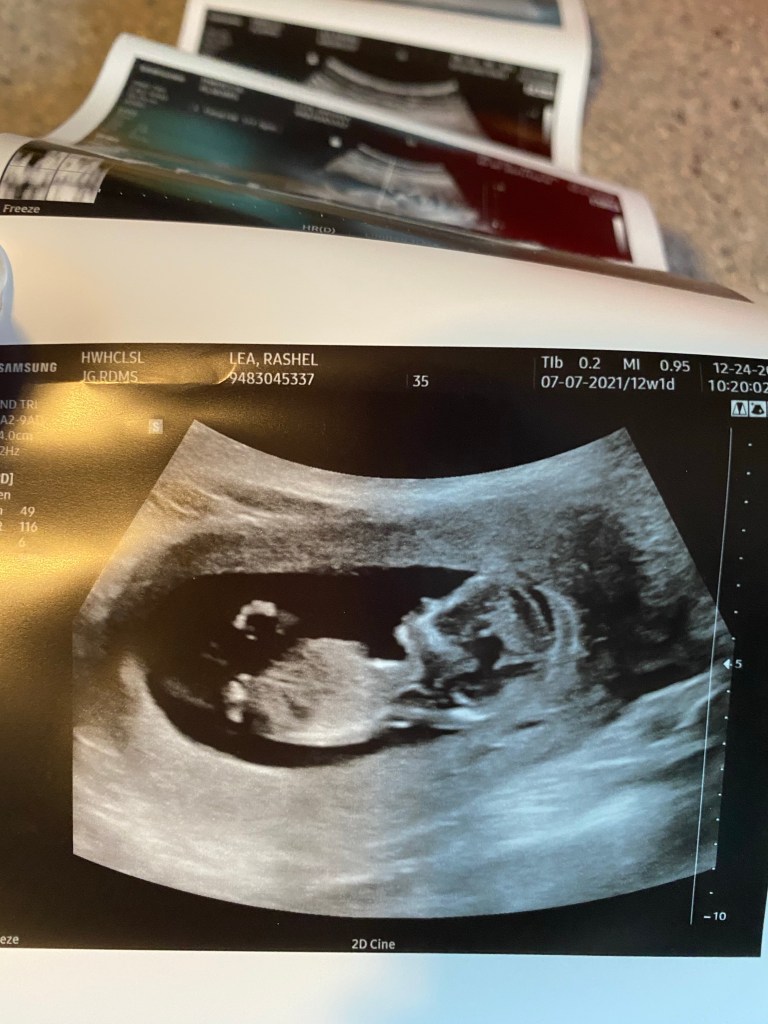

Well 12 weeks and 1 day! Wow 😳 it’s already going by so stinking fast. Im happy and sad because well obviously I just love all things pregnancy. We had a drs appointment today and we got to see sweet baby LB. He already looks perfect. A real big baby in there now. He is 6 1/2 cm they showed me. 😂 Basically he looks big and perfect on the screen but is actually super tiny in there. He has fingers sweet feet too. Actually they measured him and he looks to be measuring 12 weeks and 6 days so almost a week ahead.

It is seriously incredible to me how fast they grow and change in there. I don’t think I will ever not be just amazed by it all. Also great news guys I am officially done with meds in two days!!! I’m starting to feel the prego belly growing. I think I look like I’m 20 weeks instead of just 12 😆. Also during the ultrasound baby LB was quite the active little man. He was just kicking and playing and rolling too! Also I asked again in case anyone is wondering he is still head down!!!